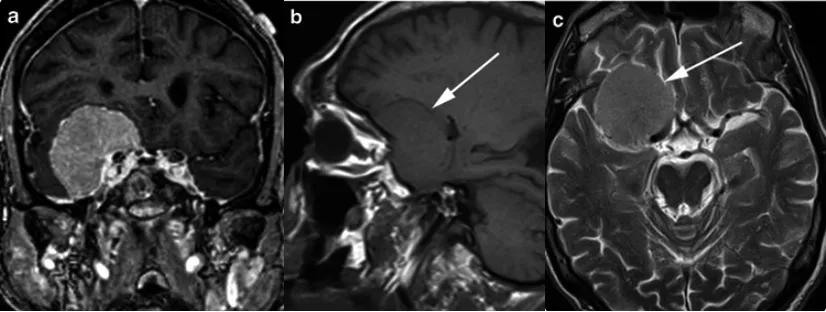

脑膜瘤是中枢神经系统肿瘤中,最具有特征性影像学表现的肿瘤。在X线和脑室造影的年代,检查结果仅起到提示作用。现在,影像学技术可以对脑膜瘤进行无创、准确地诊断,明确病灶与周围...

岩斜区位于颞骨岩部背面与枕骨斜坡部的岩斜裂汇合处,从岩骨尖至颈静脉孔。内侧至斜坡中线,外侧至第Ⅴ、Ⅶ和Ⅷ脑神经,上缘为鞍背,下缘为颈静脉孔水平;下方为枕骨大孔区。岩斜区脑...